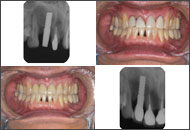

| 1ピースでの審美性の工夫(2) | ||

![]() 1999/10/04 左下6 5SM植立、2000/01/26 左下7 #568植立、2000/8/18 MBCr装着 |

![]() 2001/01/26 右上2 4LM植立、2001/10/31 右上2,右上1,左上1,左上2 MBCr着 |

![]() 2006/08/23 右上2 植立5Y1M後、左下6 植立7Y11M後、左下7 植立6Y7M後、前歯、臼歯共に審美性を保っている。右上2は、右上1,左上1,2などの天然歯と何ら遜色はない。 |